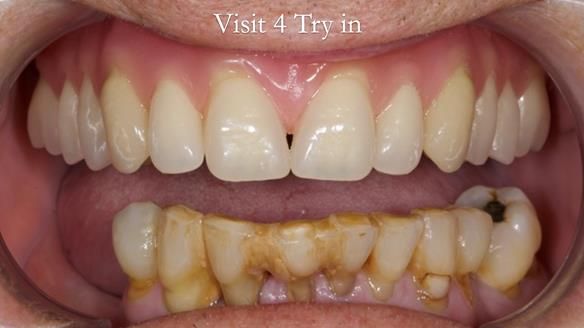

Welcome to my Newsletter 54 showing the making and fitting of dentures (a complete upper metal reinforced denture, a lower immediate partial denture and a definitive Scandinavian designed, metal based lower partial denture) for David, a 75 -year-old man. The full protocol workflow is presented including the use of dentate photographs to mimic his natural teeth.

“White in colour”

The clinical situation and treatment process is shown in detail below. I provided the clinical work. Rowan Garstang, my dental technician, provided the technical work.

Interestingly we found that the upper complete denture when finished and fitted didn’t have good enough retention for David’s satisfaction. It was relined by adding compound to the buccal flanges – to almost overextend into the sulcus to ‘create’ a sulcus, followed by using a light bodied silicone impression material. This improved the function of the C/-considerably. A lower Scandinavian hygienically designed lower RPD was also provided which helped with occlusal stability and reseating the upper denture – further improving the fit.